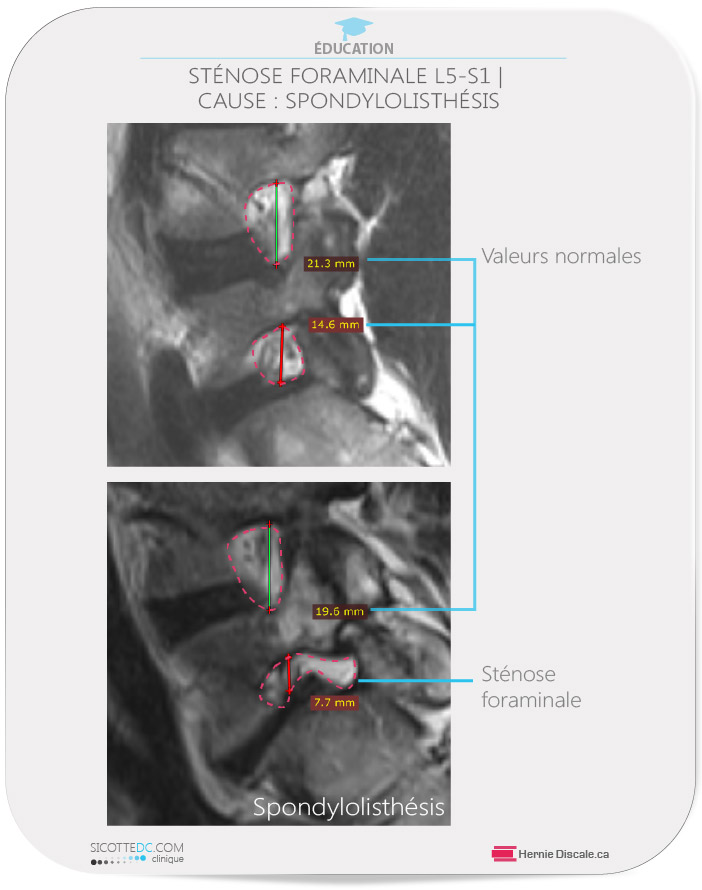

STÉNOSE FORAMINALE – CAUSE : SPONDYLOLITHÉSIS (AVEC UNE SPONDYLOSE)

Le cas ci-dessus illustre une sténose foraminale (rétrécissement du foramen) chez un homme de 52 ans. Le foramen est sténosé pour deux raisons : la destruction du disque intervertébral et la brisure des pars interarticularis de la vertèbre L5. Lorsque le rétrécissement du foramen est causé par l’avancement d’une vertèbre sur un autre, cela s’appelle une spondylolisthésis (spondyl = colonne vertébrale, listh =avancement, ésis = état).

On aperçoit ci-dessus des valeurs normales du foramen intervertébral L4-L5 : 21,3 mm et 19,6 pour patients. Par contre, le patient b souffre d’une spondylolisthésis isthmique congénitale (appelée aussi spondylolyse) causé par la brisure ou fracture (une lyse) dans la région lombaire, ce qui empêche l’avancement normal de la vertèbre supérieure. Au fil des années, le disque de notre patient a subi les effets d’une aberration biomécanique qui a eu comme effet de diminuer l’espace foraminal. La valeur de 7,7 mm classe la compression foraminale parmi les compressions sévères. Les soins Cox® soulagent le patient de l’engourdissement sur la face antérieure avant de la cuisse. Les conseils du Dr Sicotte ont encouragé le patient à abandonner tous les sports de compression et à modifier son ergonomie au travail. Les modifications suggérées au patient lui ont permis de jouir pleinement de la vie.